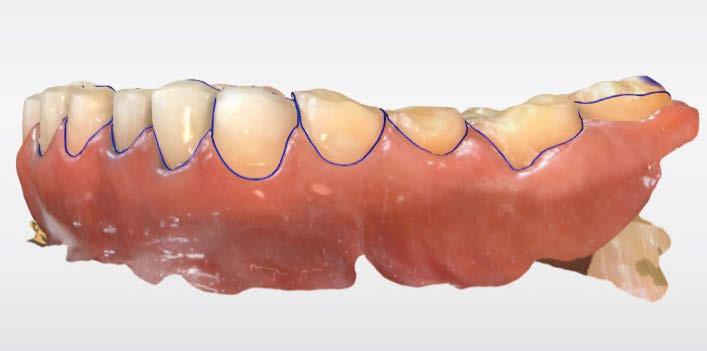

Se obtuvieron modelos de estudio (Figuras 3-6) digitales mediante un escáner confocal de luz azul estructurada (PrimeScan, Dentsply Sirona) y se planificó un protocolo de desgaste mínimamente necesario y conservador de las estructuras

dentarias, cumpliendo parámetros biológicos, terapéuticos, mecánicos y estéticos. Después se realizó un modelado digital retrospectivo (Figuras 7-11) para generar modelos impresos 3D para realizar el mock up funcional, estético y como guía para las preparaciones (Figuras 12-15). Con ello, se efectuaron las preparaciones dentarias y los registros intermaxilares y, posteriormente, se digitalizaron ambos maxilares (Figuras 16-21)

Figura 5. Impresión digital, vista superior derecha. Figura 3. Escaneado maxilar superior zona anterior. Figura 4. Impresión digital, vista superior izquierda.

Figura 6. Impresión digital, vista oclusal, maxilar inferior.